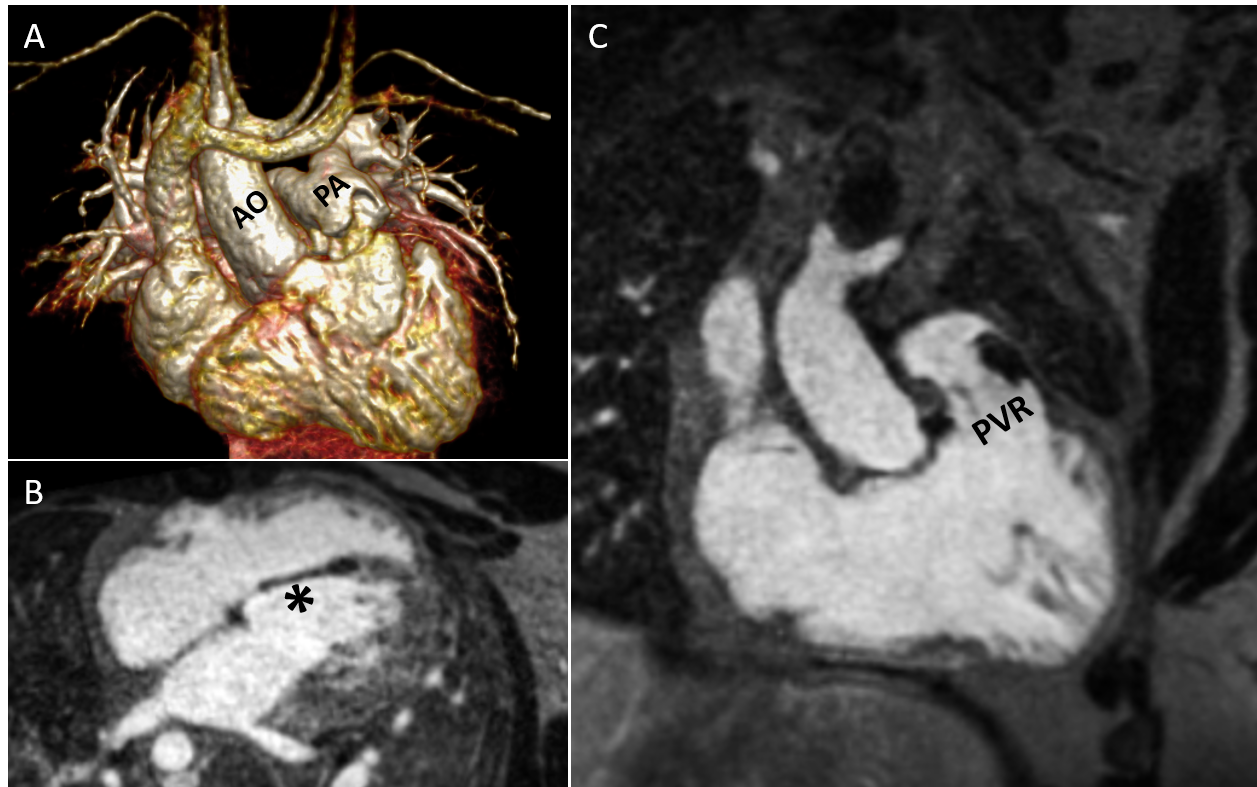

Diagnostic Techniques and Their Most Important Findings: In addition to standard cine and phase contrast imaging, the previously described image-based navigator (iNAV)/variable density Cartesian with spiral-like trajectory (VD-CASPR) research framework was utilized for contrast enhanced (CE) inversion recovery MRA[1] on a 1.5T scanner (MAGNETOM Sola , Siemens Healthineers, Forchheim, Germany) . Segmental anatomy was S, D, S. Relevant cardiac findings included a patch in the interventricular septum consistent with prior defect repair, right-sided aortic arch, and bioprosthetic pulmonary valve with mild regurgitation (regurgitant fraction of 15%) (Fig 1). Left and right ventricular volumes were within normal limits (LV EDVi 86 ml/m², RV EDVi 108 ml/m²), with mildly reduced LVEF (46%) and low-normal RVEF (48%).

Fig 1- 37-year-old man, with a history of Tetralogy of Fallot. (A) Normal configuration of the ascending aorta (AO) and pulmonary artery (PA) with right sided aortic arch. (B) A patch related to previous ventricular septal defect repair (asterisk) is present.. (C) A bioprosthetic valve is present in the pulmonary valve position (PVR).